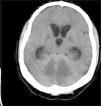

Presentamos el caso de un varón de 38 años con antecedentes de esquizofrenia paranoide que ingresó en nuestro hospital tras ser encontrado inconsciente en un coche cerrado, inhalando el humo del tubo de escape, junto a 2 blíster vacios de benzodiacepinas. A la exploración inicial destacaba baja saturación de oxígeno y un Glasgow de 3. Los valores de carboxihemoglobina eran del 23%. Se realizó una TAC de cráneo inicial (fig. 1) que mostró hipodensidades difusas en hemisferios cerebelosos, sustancia blanca temporobasal bilateral y ganglios basales. Tras una mejora inicial durante las primeras 48h, en las cuales el paciente alcanzó un Glasgow de 10, presentó un empeoramiento clínico con imágenes en TAC de cráneo de severa dilatación de ventrículos laterales y tercer ventrículo, compatible con hidrocefalia obstructiva, por lo que precisó válvula de derivación externa. Posteriormente, en una RMN craneal de control (fig. 2) se comprobó la resolución de la hidrocefalia. Persistían lesiones bihemisféricas que afectaban de manera extensa a sistema límbico, hipocampo, fórnix y áreas temporobasales, lóbulos frontales y parietales y también a ambos hemisferios cerebelosos, todo ello compatible con lesiones anóxico-isquémicas bilaterales múltiples secundarias a intoxicación por CO. Superada la fase aguda, el paciente persistía con deterioro severo de funciones corticales asociado a ataxia de la marcha y síndrome acinético-rígido hemicorporal, sin evidencia de mejoría.